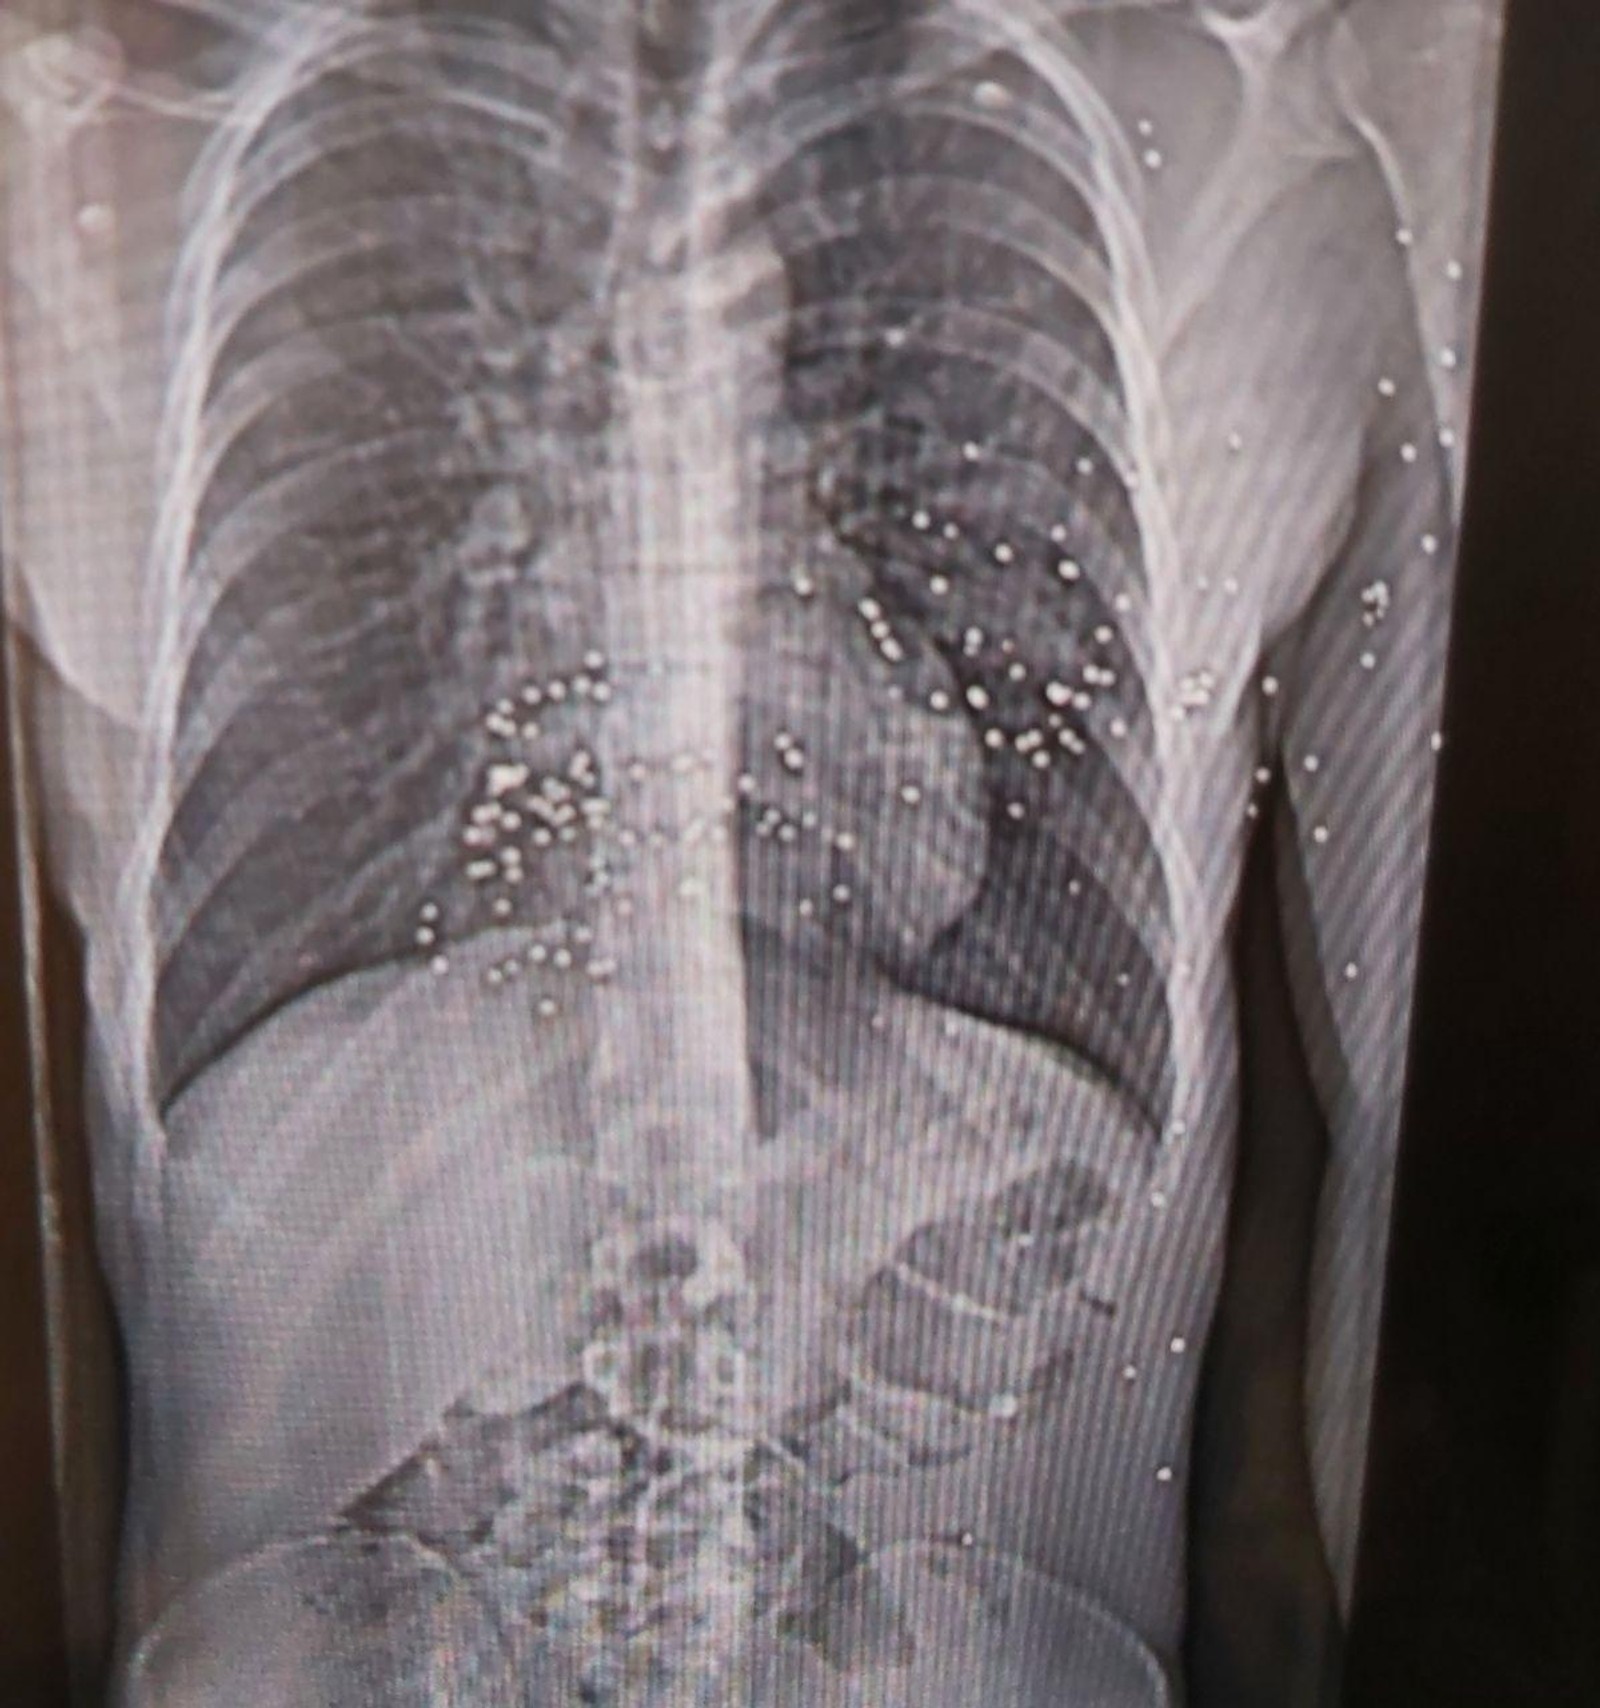

نیویورکر نوشت ‏اعضای کادر درمان در هفته‌های اخیر خود به مستندسازی شواهد حملات حکومت به مردم ایران پرداخته‌اند و برخی مدارک از جمله تصاویر سی‌تی‌اسکن مجروحان را در اختیار این مجله قرار داده‌اند.

نرگس این وضعیت را «جهنمی» توصیف کرد: نوجوانی ۱۴ ساله با پاهایی نحیف که با ساچمه‌های فلزی هدف قرار گرفته بود؛ مردی با حفره‌ای به اندازه توپ تنیس در ساق پا که او در بخیه‌ زدن آن کمک کرد.